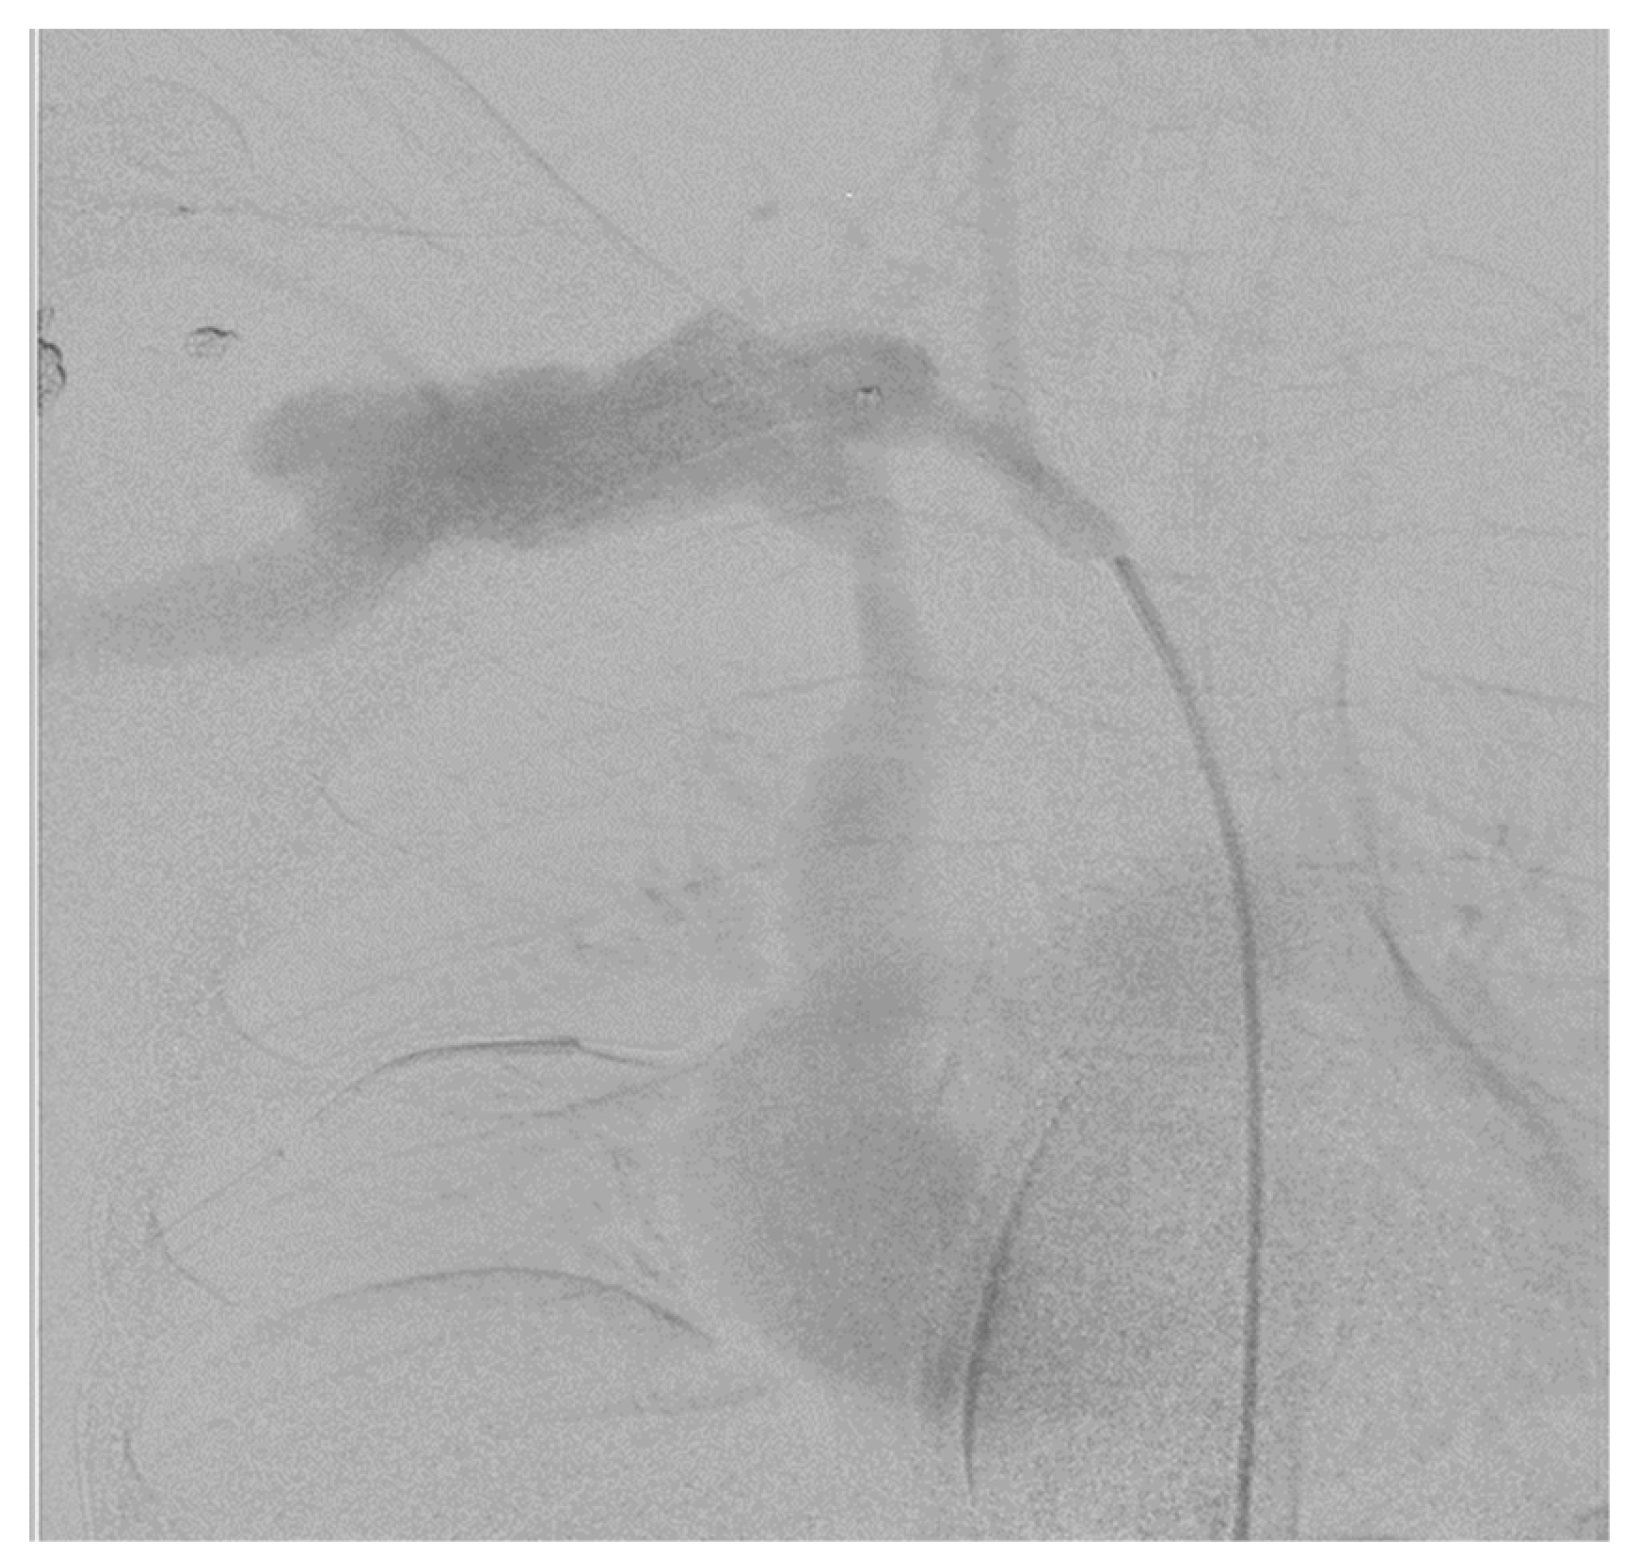

3.8. Digital Subtraction Angiography (DSA)